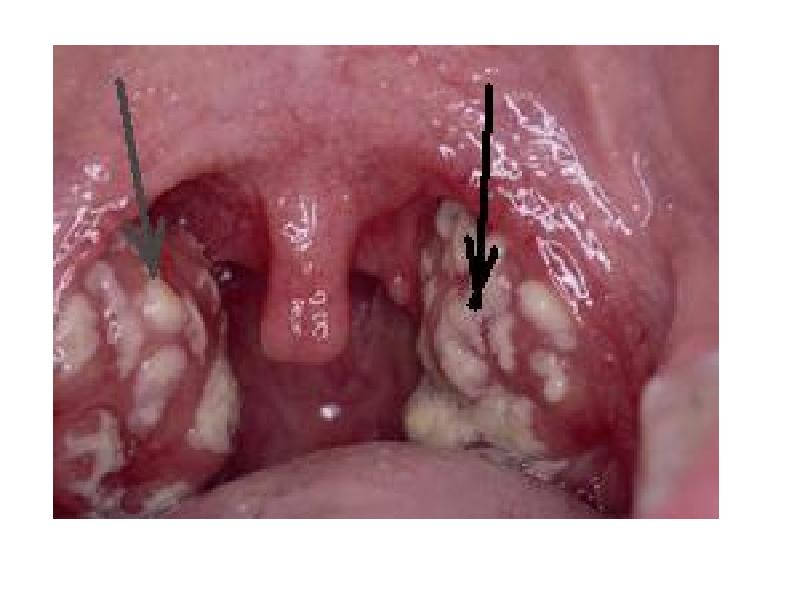

- 19. Лакунарная ангина Лакунарная ангина протекает с симптомами аналогичным фолликулярной, но более

- 21. Двусторонняя лакунарная ангина